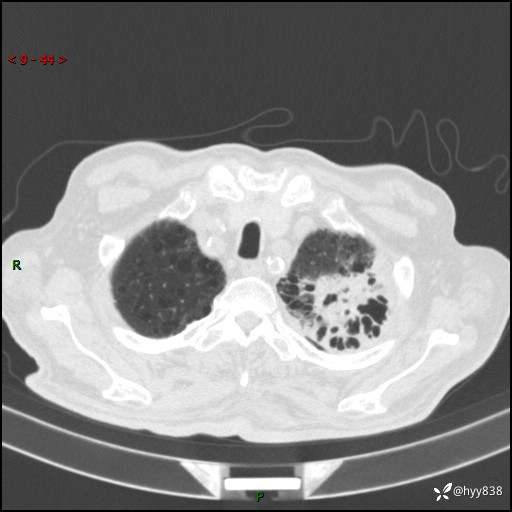

老年男性,间断咳嗽咳痰20余年,加重伴发热1天。呼吸科疑难病例讨论---结果公布

主诉:间断咳嗽咳痰20余年,加重伴发热1天

简要病史:家属代诉患者于20余年前无明显诱因出现咳嗽咳痰,痰为白色泡沫状,未行特殊治疗,不伴胸痛、胸闷、气喘、咳血等不适,1天前上午患者无明显出现发热,查体温39℃,伴咳嗽,咳痰无力,自行予以物理降温对症治疗,今晨2点左右再次出现发热,体温达40℃,自行服用复方氨酚烷胺对症治疗,凌晨3点左右复测体温38.2℃,现患者为求进一步诊治于今日就诊于我院门诊,行胸部CT提示双肺感染,遂以“肺部感染”收入我科。 患者本次起病来精神、食欲、睡眠欠佳,体力下降,体重无明显变化。

辅助检查:CT

胸部CT平扫